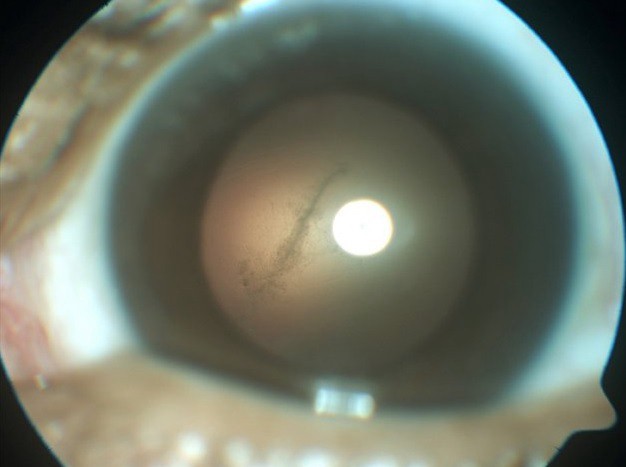

Sam Cordero debió ser operado de urgencia después de que le descubrieran que tenía un gusano en su ojo izquierdo, en la ciudad de Tampa, en Estados Unidos.

"Veo un pequeño punto negro y sólo en el ojo izquierdo. Veo que algo se mueve de izquierda a derecha. Cuando sale el sol, me molesta mucho", dijo el hombre al realizar una consulta médica.

Luego de los estudios respectivos, los profesionales encontraron que el paciente tenía el gusano taenia solium, más comúnmente llamado tenia de cerdo.

En algunos casos, el parásito viaja por el torrente sanguíneo a través de los intestinos de la persona afectada y acaba incrustrándose en el cerebro o en el globo ocular de las personas afectadas, según RT.

De acuerdo con ese medio, los médicos pudieron extraerle a tiempo el parásito ya que, si el gusano hubiera muerto, la inflamación podría haber provocado que Cordero se quedara ciego de ese ojo.